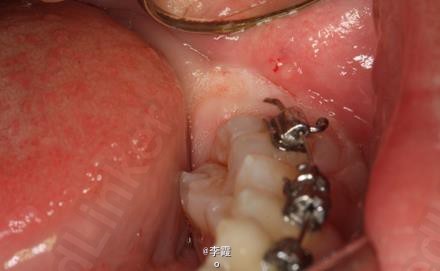

患者、马xx、15岁,主诉:牙齿不齐,要求正畸治疗。 转诊外科行下颌升支处种植体支抗直立下颌磨牙。通过患者的术前影像资料,47牙冠远中有部分骨质覆盖牙冠,采取翻瓣导萌直立磨牙。37采取电刀环切导萌直立磨牙。

恢复良好,患者满意。